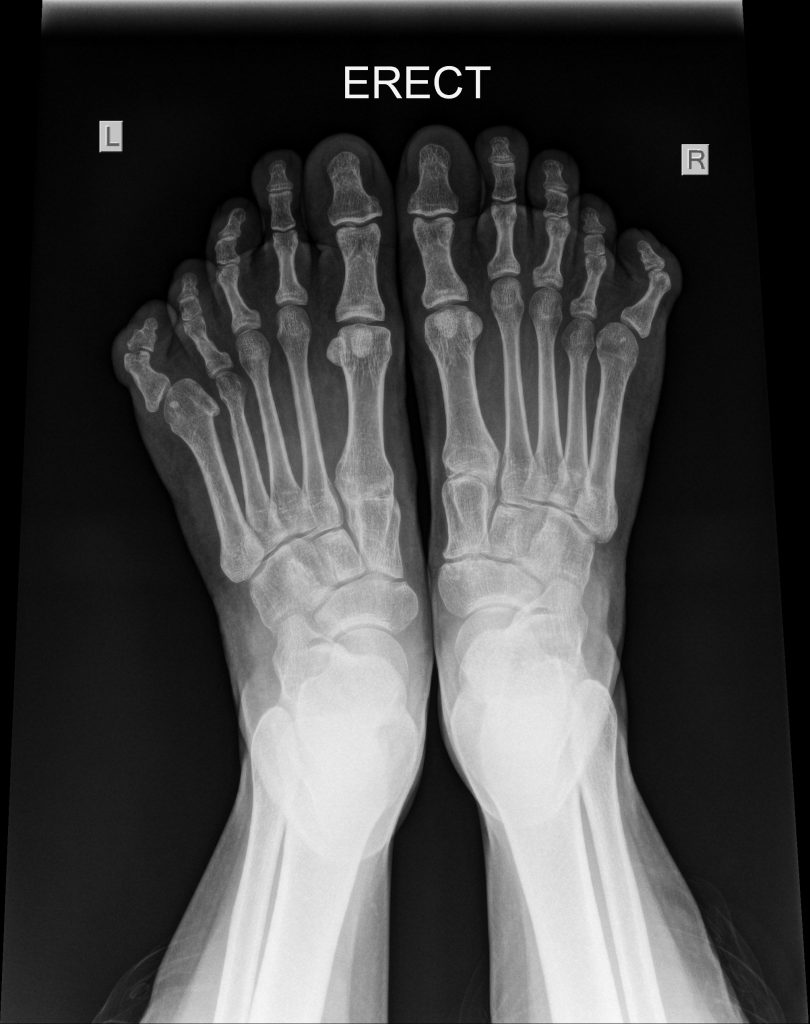

ENLARGEMENT OF THE FIFTH METATARSAL

I recently had the privilege of seeing a patient with an interesting enlargement of the fifth metatarsals of both feet. The problem was not so much pain as difficulty with shoewear.

I elected to shorten the metatarsals and stiffen the proximal joint of the little toes so the form of the foot could approach normality.